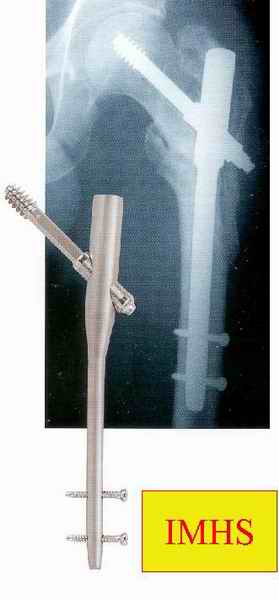

слайды:

Long TFN

Short TFN

IMHS

DePuy Trochanteric Nail